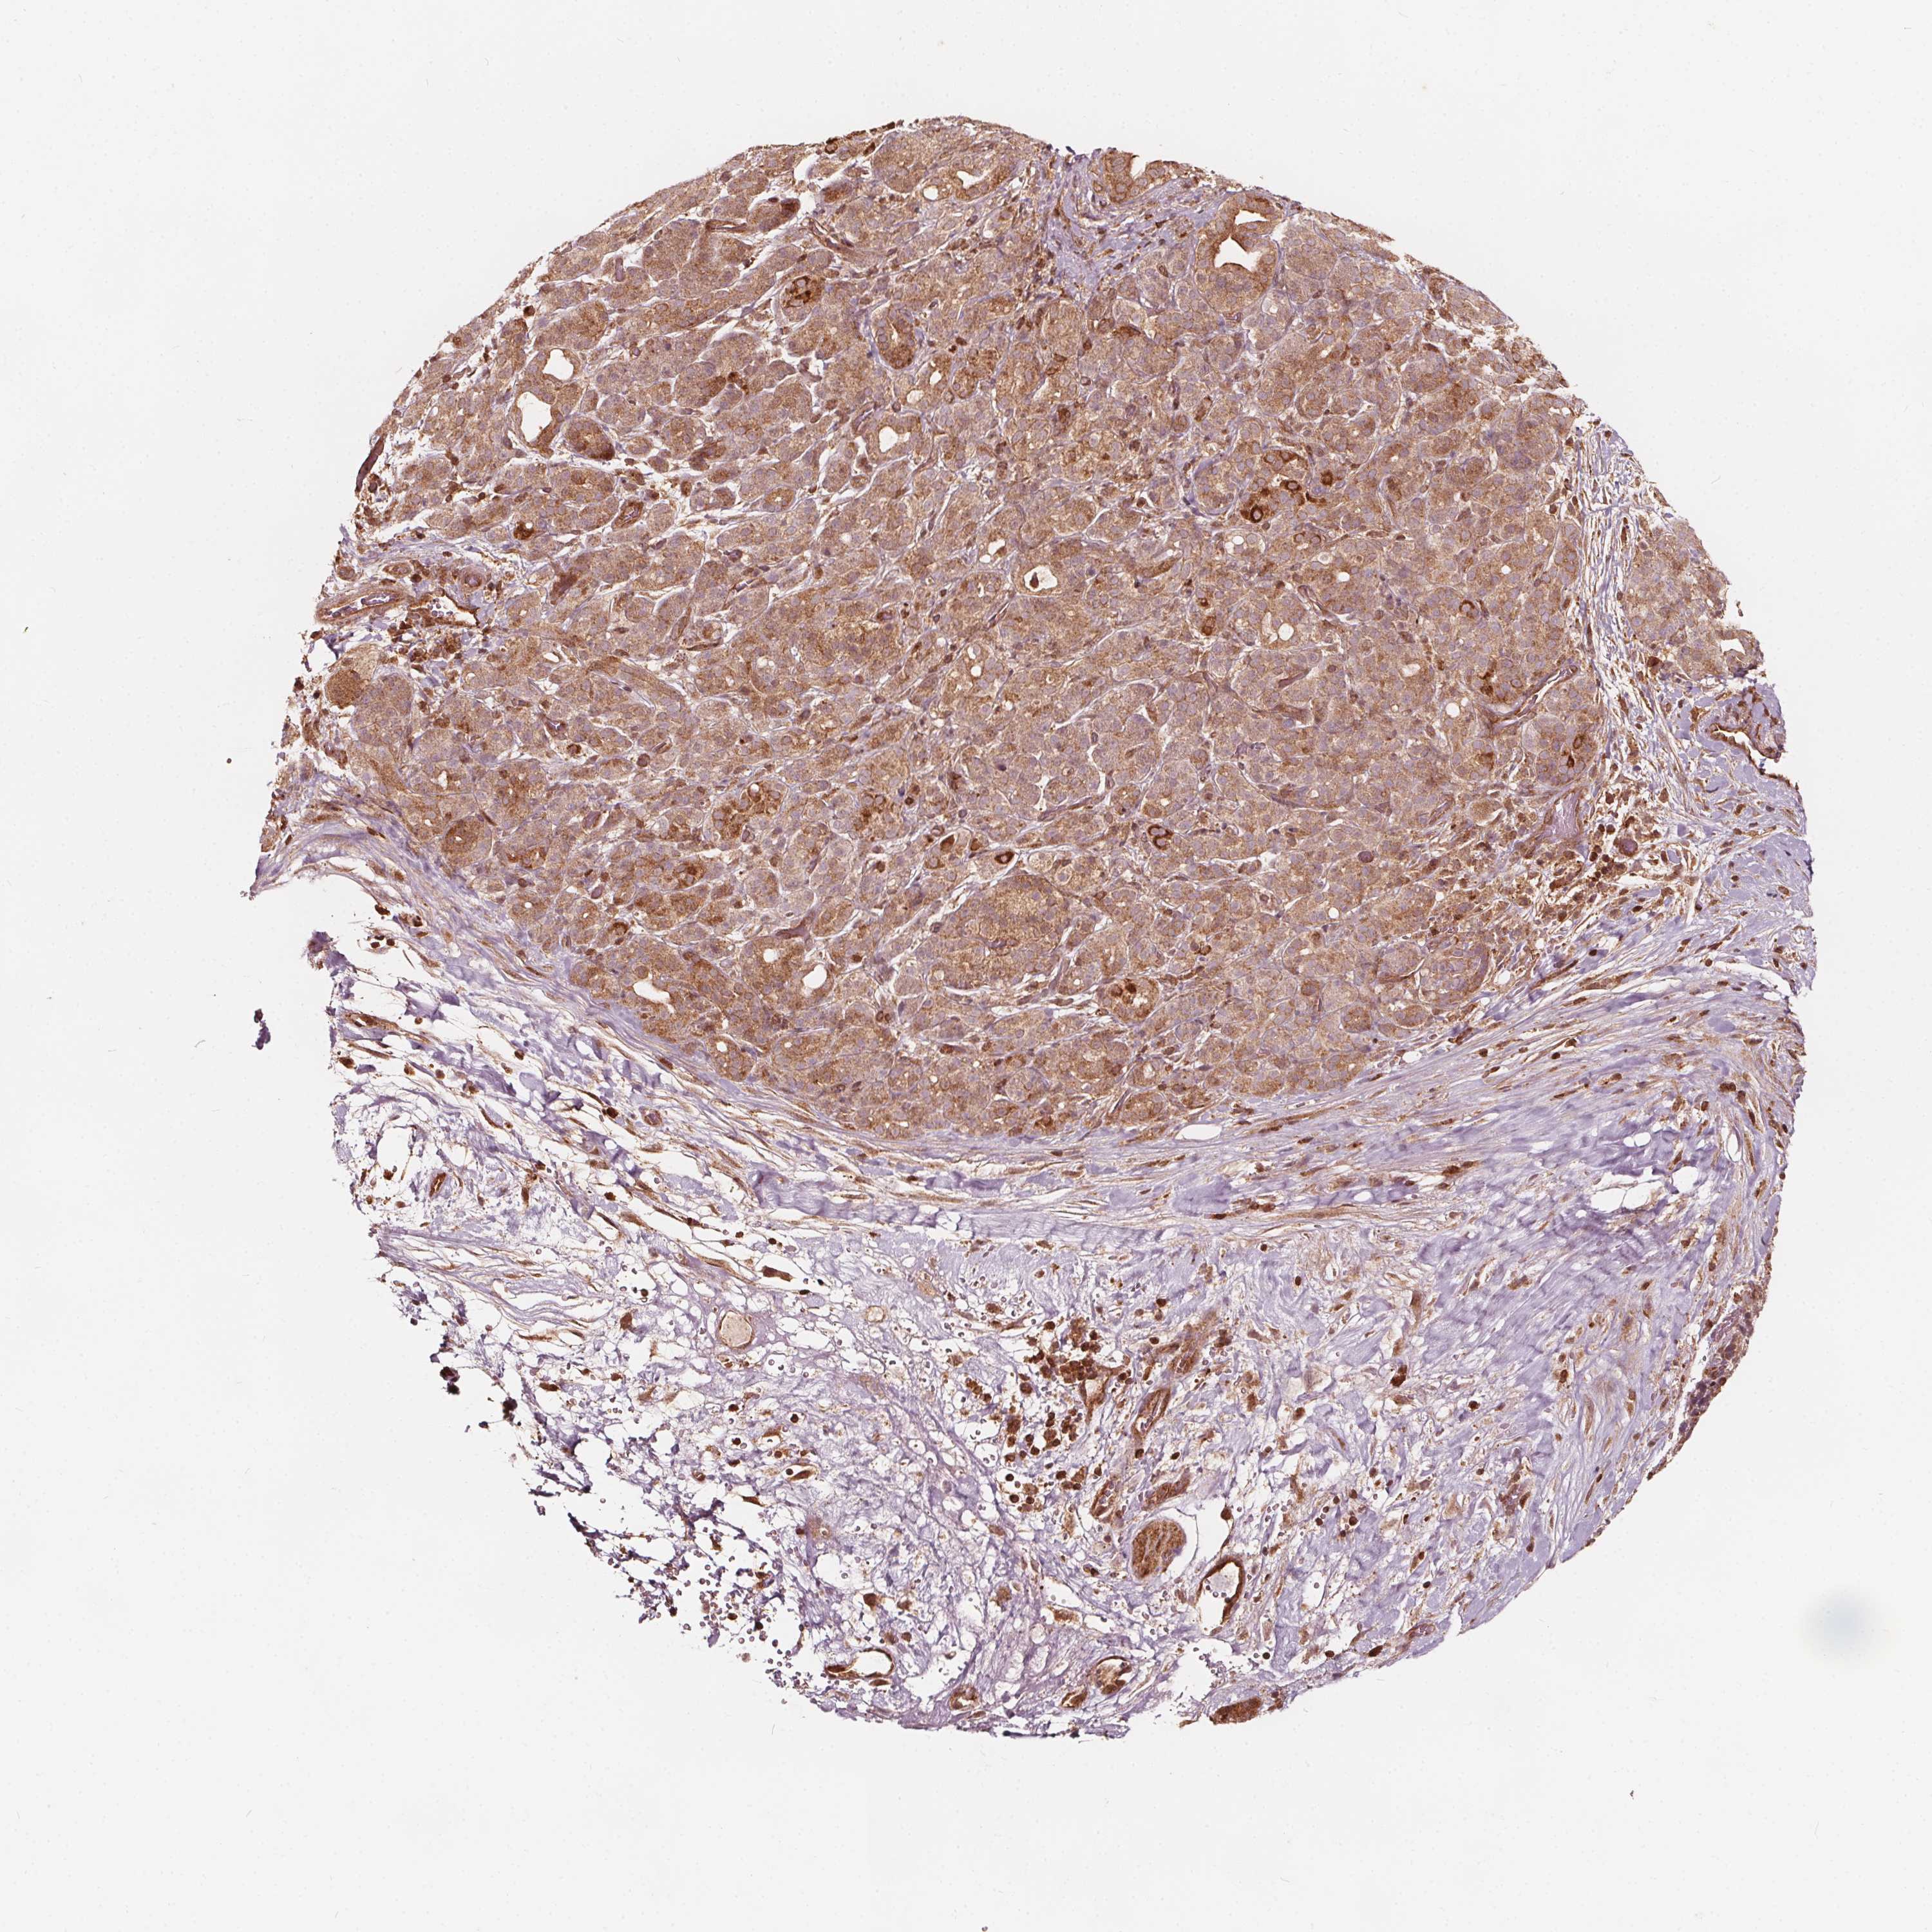

PANCREATIC CANCER - Protein expressioni

A mouse-over function shows sample information and annotation data. Click on an image to view it in a full screen mode. Samples can be filtered based on level of antibody staining by selecting one or several of the following categories: high, medium, low and not detected. The assay and annotation is described here.

Note that samples used for immunohistochemistry by the Human Protein Atlas do not correspond to samples in the TCGA dataset.

Antibody stainingi

Antibody staining in the annotated cell types in the current human tissue is reported as not detected, low, medium, or high, based on conventional immunohistochemistry profiling in selected tissues. This score is based on the combination of the staining intensity and fraction of stained cells.

Each image is clickable and will lead to virtual microscopy that enables deeper exploration of all samples and also displays staining intensity scores, fraction scores and subcellular localization as well as patient and tissue information for each sample.

Antibody CAB033674

Antibody CAB069477

Staining

High

Medium

Low

Not detected

Intensity

Strong

Moderate

Weak

Negative

Quantity

>75%

75%-25%

<25%

None

Location

Nuclear

Cytoplasmic/membranous

Cytoplasmic/membranous,nuclear

Adenocarcinoma, NOS